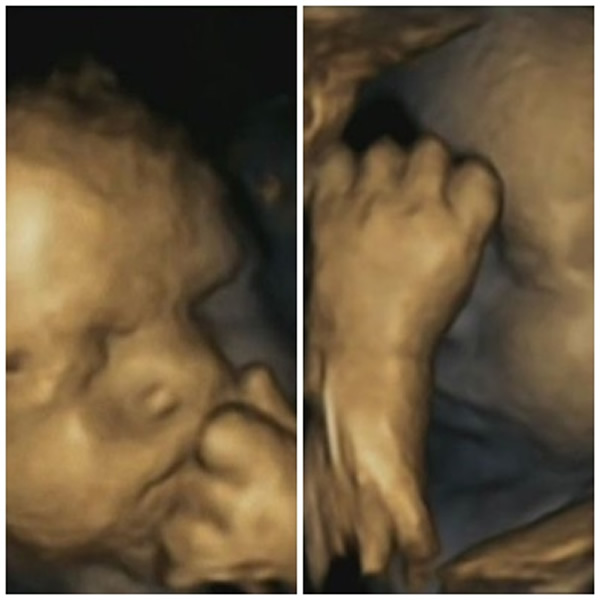

4D扫瞄图片发现母亲发愁时,胎儿摸脸的次数也增加。

英国达勒姆大学早前为15名孕妇分别进行4次4D超声波扫描,并记录她们该月内的压力水平,竟发现当准妈妈心情欠佳、感到压力时,胎儿不但会同样愁眉不展,而且伸手摸脸的次数也会增加。

研究员相信这显示胎儿能感受到母体的皮质醇变化,从而作出相应举动。参与研究的7名男性胎儿和8名女性胎儿共摸脸342次,不论胎儿性别都同样受到母亲情绪影响。